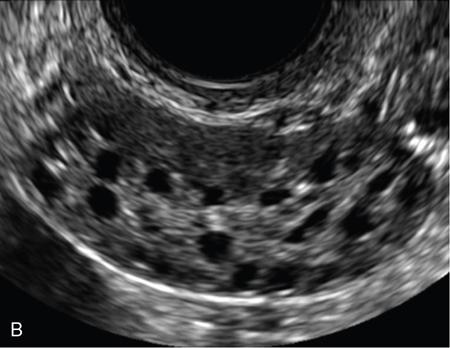

• Average number of follicles in longitudinal and transverse planes is determined (Fig. 11.20.1.2).

3. 3. 3D manual mode – reproducibility is better compared with 2D methods (Fig. 11.20.1.3).

Image

Fig. 11.20.1.2 (A) Antral follicles by 2D USG without harmonics. (B) Antral follicles by 2D USG with harmonics.